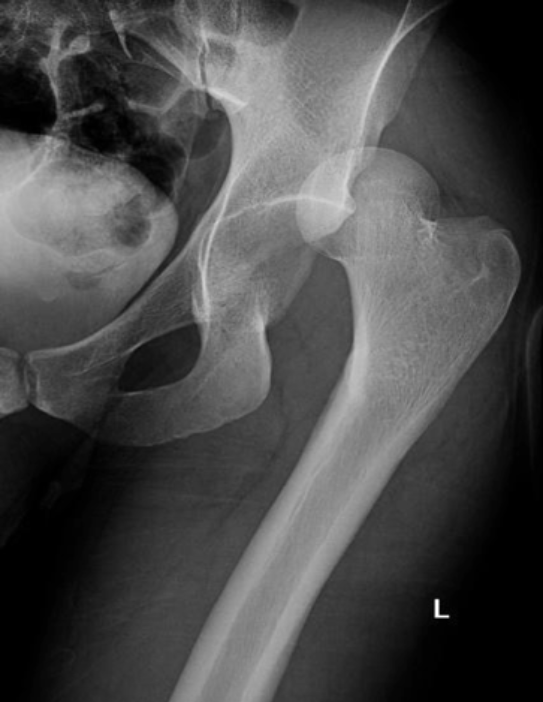

How do you do a lateral hip?

If no fracture suspected and pt able → frog leg hip

If fracture suspected → cross-table hip aka Danelius-Miller method (shoot straight into the crotch)

If a patient has a broken hip, what x-rays should you do?

Some kind of AP (single or full pelvis), cross-table hip, and 1V chest

How to hang a cross-table hip x-ray?

Entire acetabulum must be visible, lay image so butt is down and pubic symphysis is up

Results from the loss of blood supply - the femoral head is the most frequent site of it - often necessary to obtain two radiographs in patients with this condition. The first is taken with normal density, whereas the second is made with increased kVp to allow for adequate penetration of the more opaque ischemic bone.

Ischemic Necrosis

Associated with ischemic necrosis of bone. Ischemia results from poor blood supply to the bone. Affects the epiphyses and may be mistaken for tuberculosis of the skeletal system. Tends to occur in males between the ages of 5 to 10 years and often follows injury to the affected hip. Radiographically the bone in the center of the epiphysis is fragmented and the head of the femur is flattened.

Legg-Perthes Disease